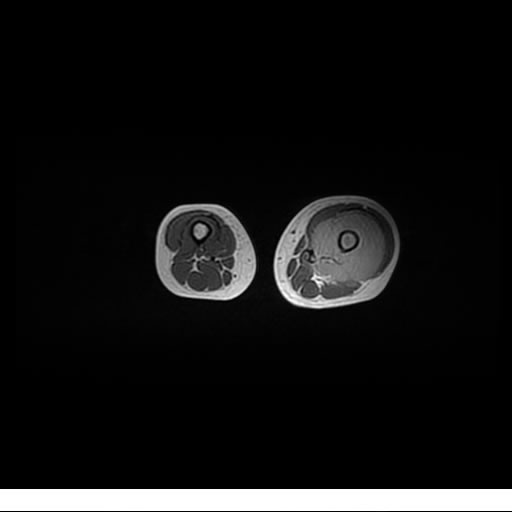

Se realiza estudio de MRI de muslo izquierdo en diferentes planos, con secuencias de Spin Echo, GRE; ponderadas a T1 y a T2, se utilizan pulsos de saturación de grasa y se administra medio de contraste IV a base de Gadolinio en base al peso del paciente.

La diáfisis femoral izquierda muestra reacción perióstica importante, se extiende desde el cuello del fémur, invade trocánteres, diáfisis femoral, medial y distal, es compatible con un proceso infeccioso óseo, el complejo muscular del muslo se ve edematizado.

Lesión de señal heterogénea en secuencias T1 (hipointensa) y T2/STIR (hiperintensa), que refleja necrosis, hemorragia y contenido celular diverso.

Realce intenso y heterogéneo tras la administración de contraste (gadolino), lo que indica vascularización tumoral.

Compromiso de la médula ósea adyacente y de estructuras vecinas, como músculos y neurovasculatura.

Posible presencia de edema óseo y necrosis central.